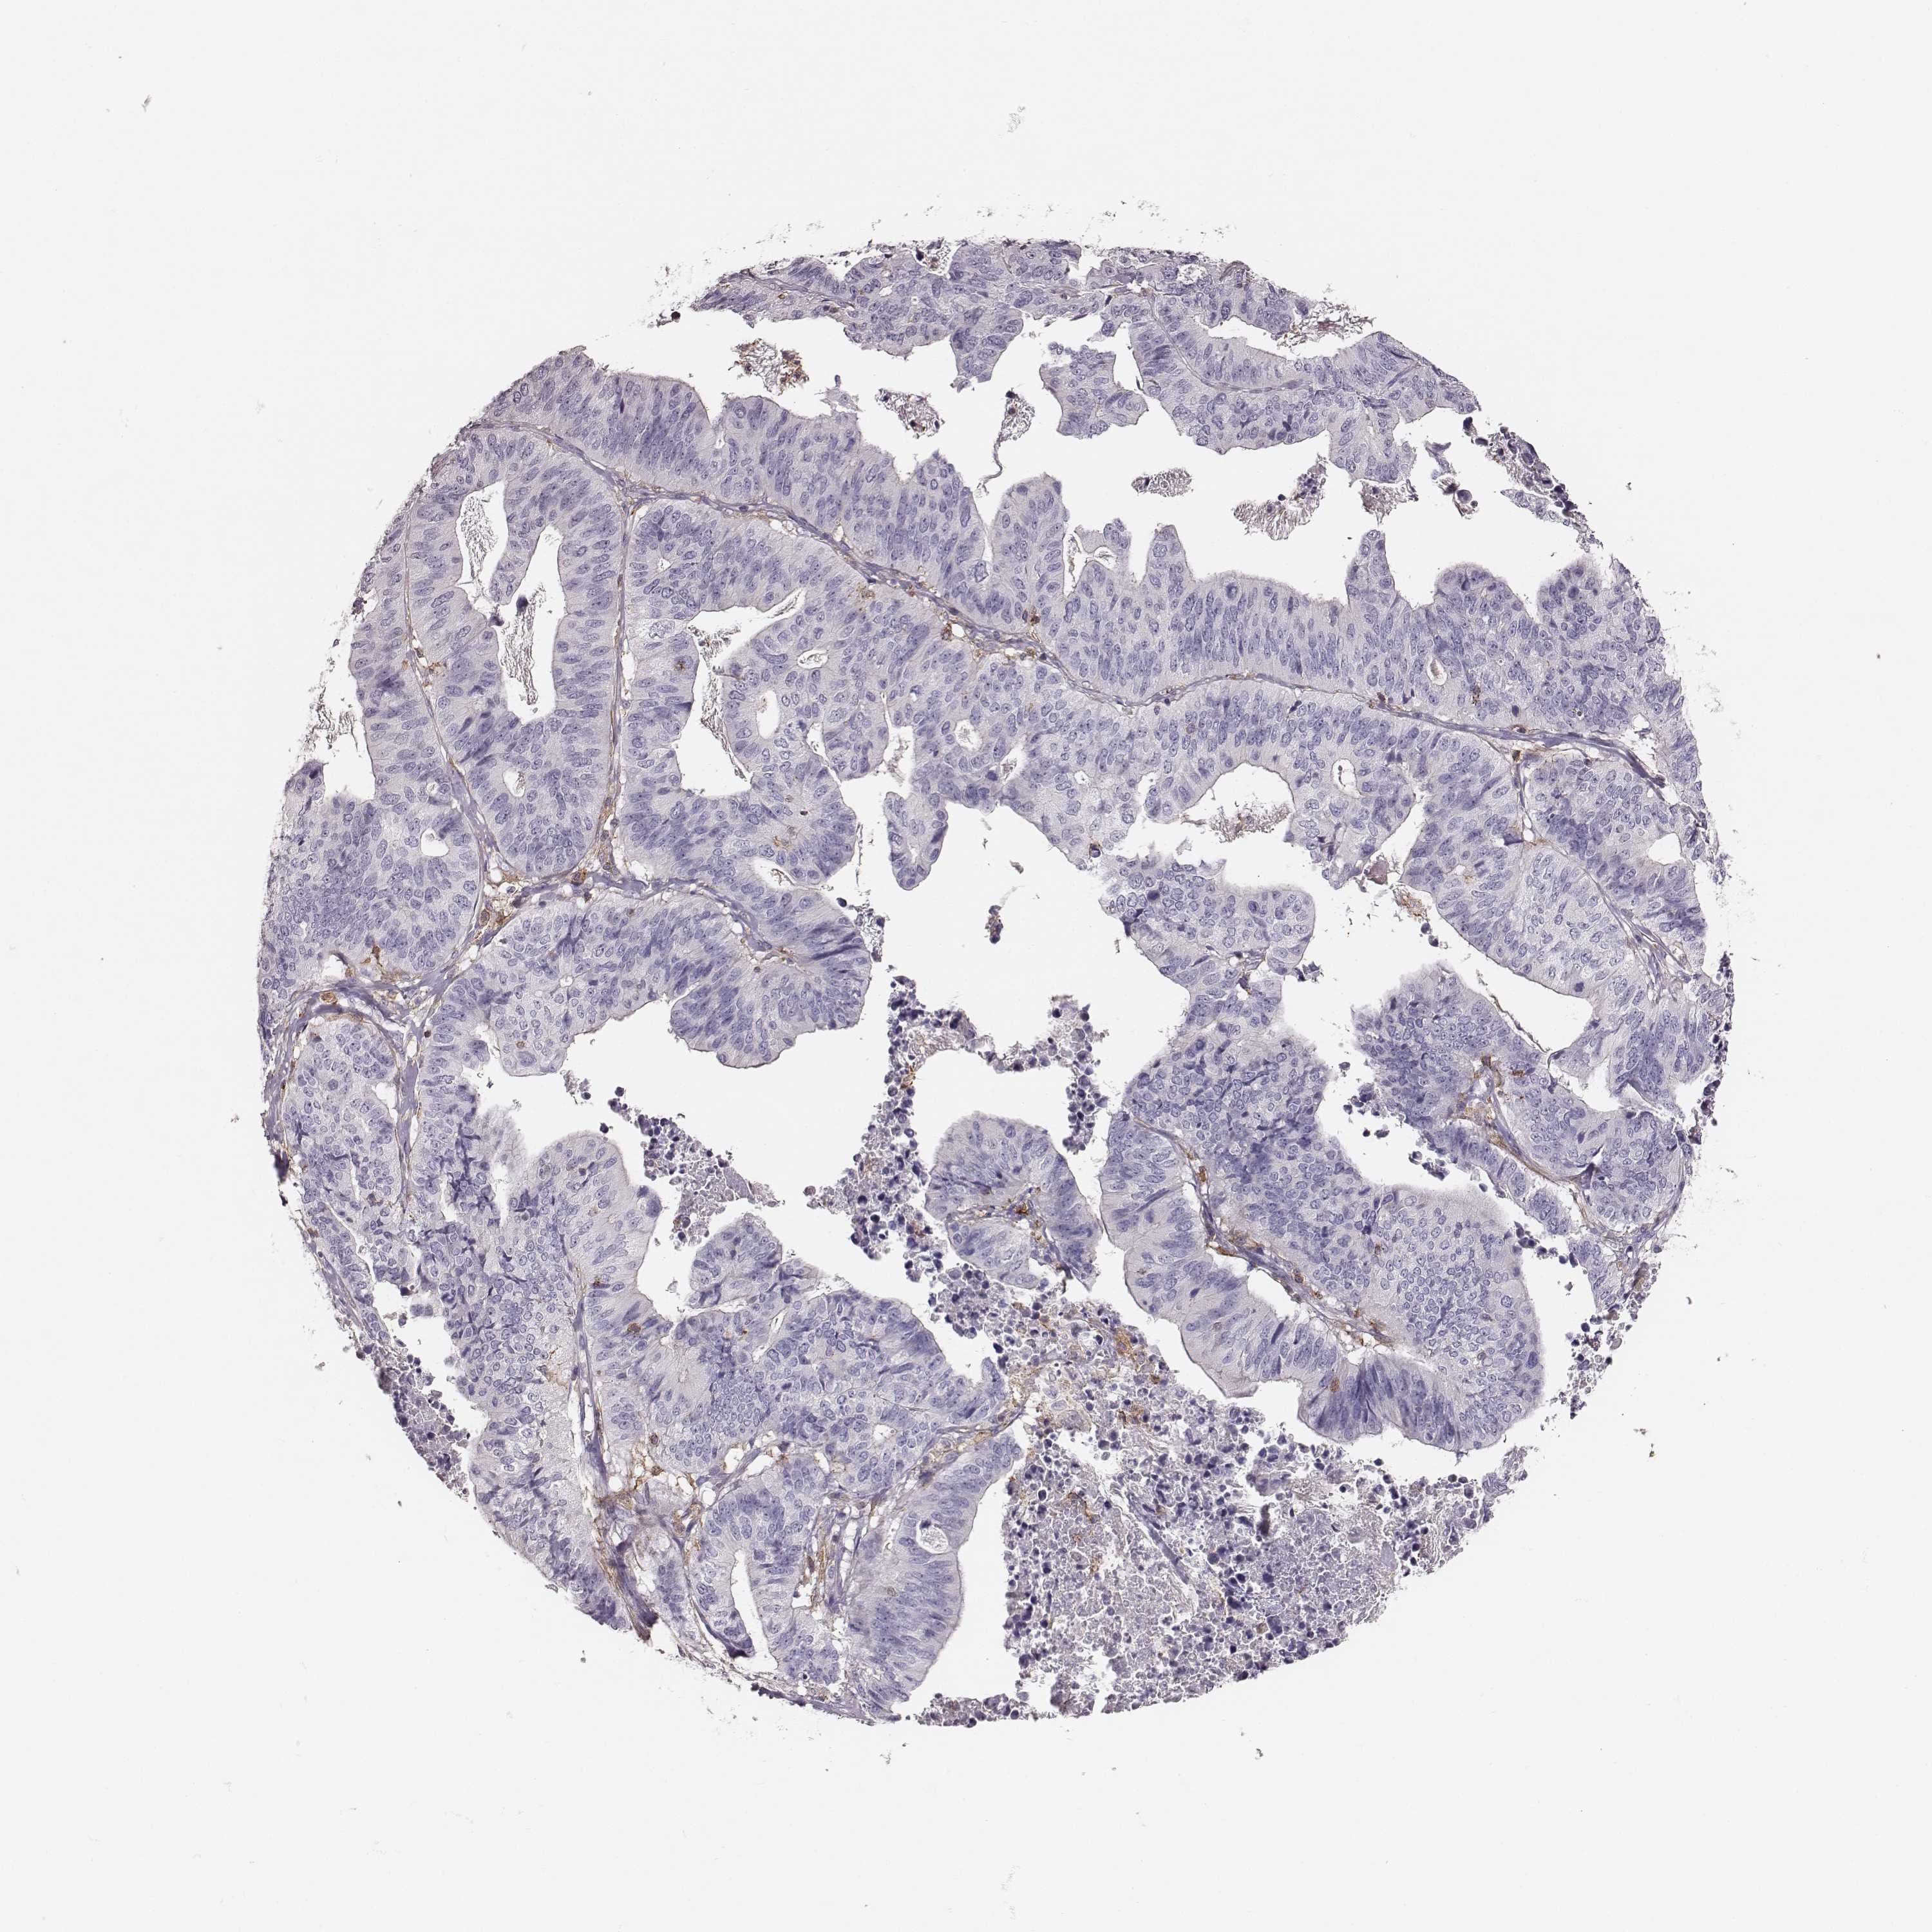

STOMACH CANCER - Protein expressioni

A mouse-over function shows sample information and annotation data. Click on an image to view it in a full screen mode. Samples can be filtered based on level of antibody staining by selecting one or several of the following categories: high, medium, low and not detected. The assay and annotation is described here.

Note that samples used for immunohistochemistry by the Human Protein Atlas do not correspond to samples in the TCGA dataset.

Antibody stainingi

Antibody staining in the annotated cell types in the current human tissue is reported as not detected, low, medium, or high, based on conventional immunohistochemistry profiling in selected tissues. This score is based on the combination of the staining intensity and fraction of stained cells.

Each image is clickable and will lead to virtual microscopy that enables deeper exploration of all samples and also displays staining intensity scores, fraction scores and subcellular localization as well as patient and tissue information for each sample.

Antibody HPA004835

Antibody HPA073497

Antibody CAB009321

Antibody CAB075747

Staining

High

Medium

Low

Not detected

Intensity

Strong

Moderate

Weak

Negative

Quantity

>75%

75%-25%

<25%

None

Location

Nuclear

Cytoplasmic/membranous

Cytoplasmic/membranous,nuclear

Adenocarcinoma, NOS

Adenocarcinoma, High grade